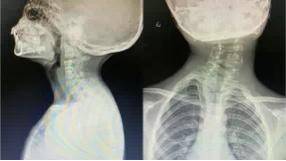

7岁女孩颈椎反张失稳x片

图片尺寸1100x1200